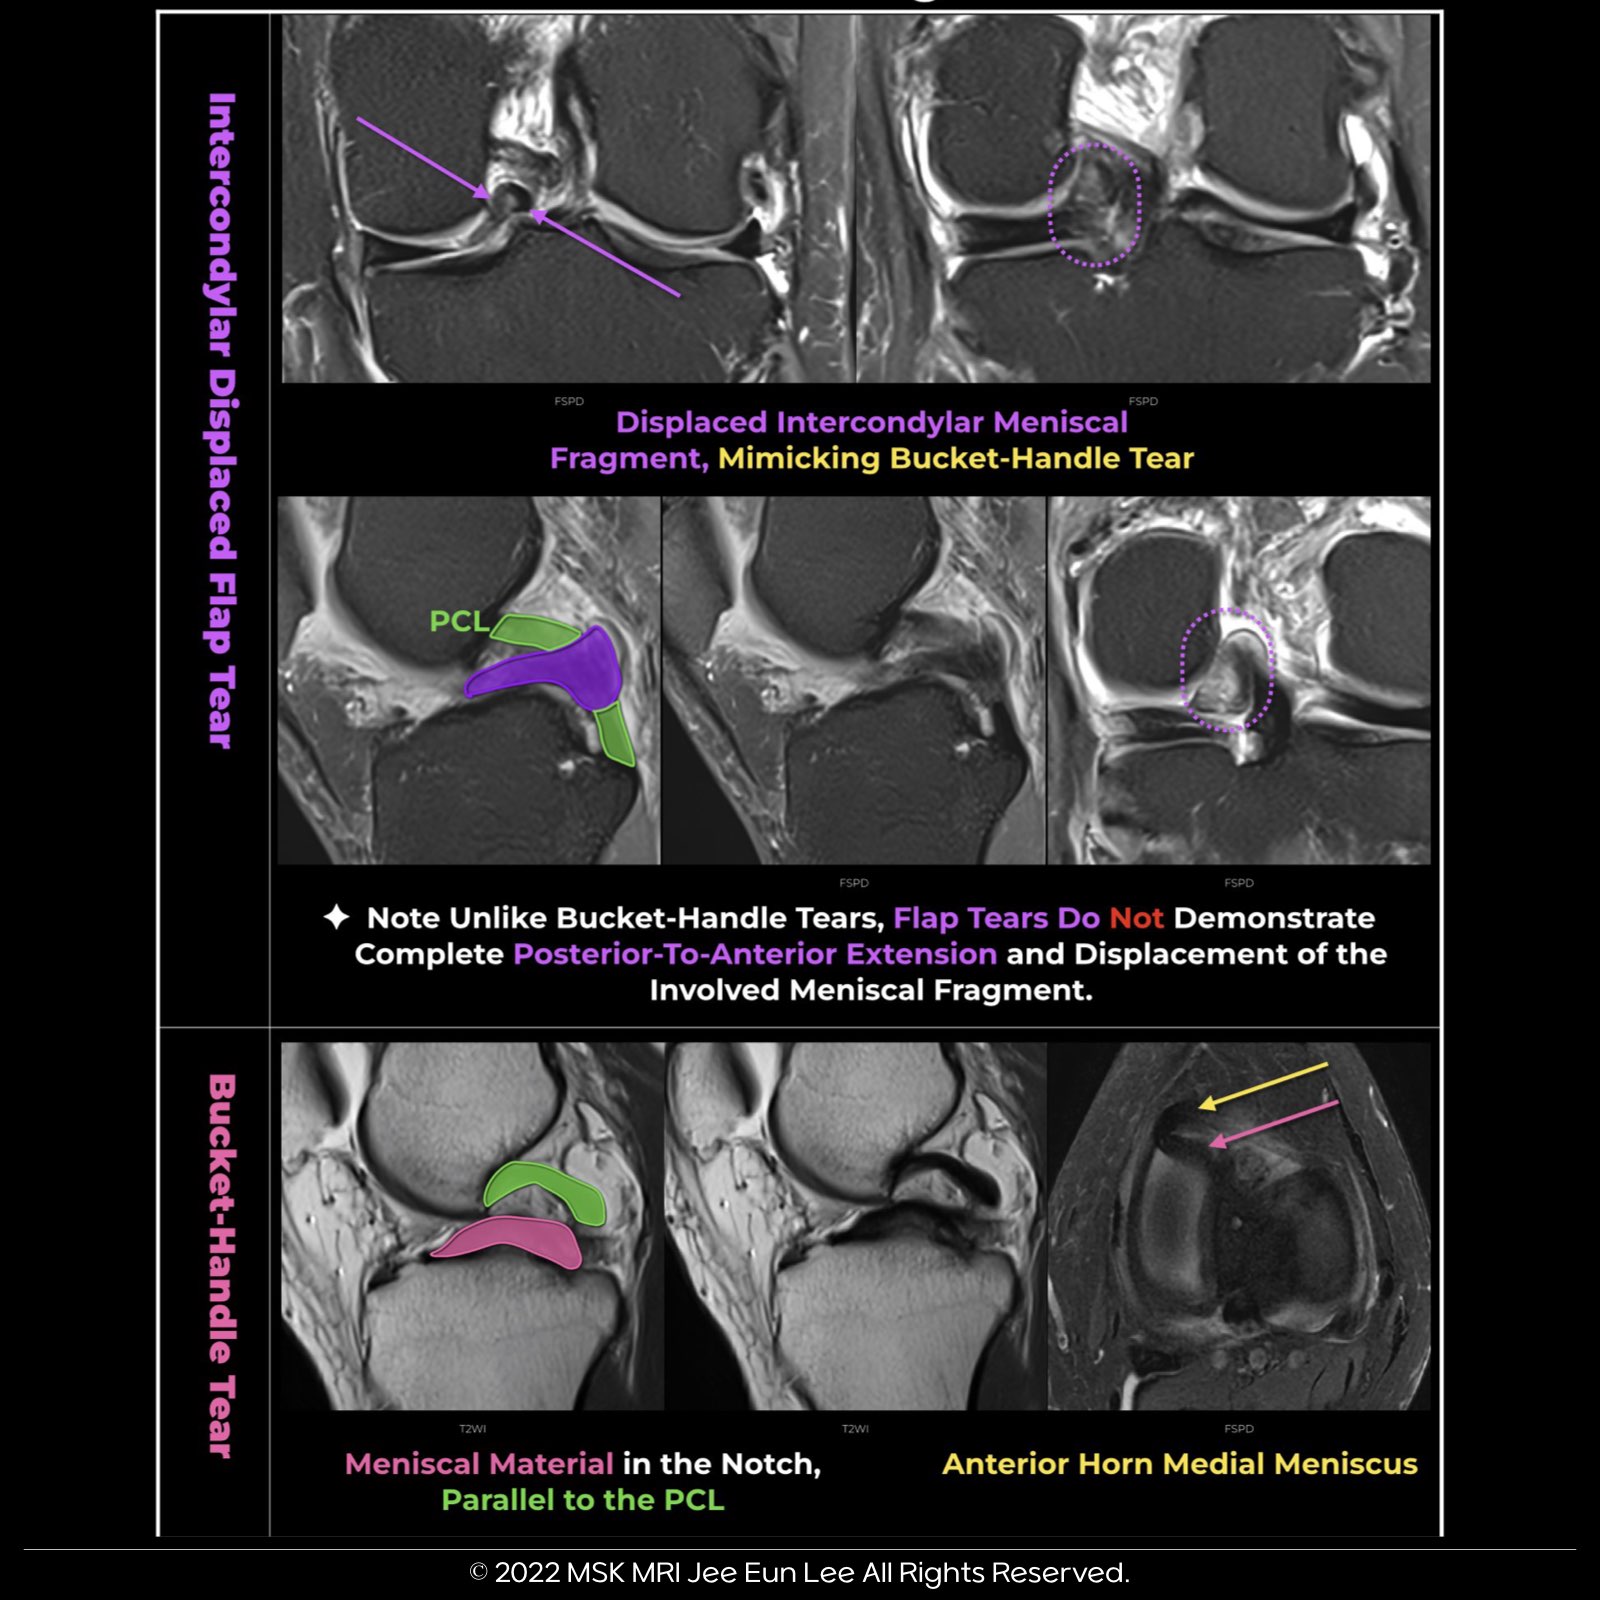

Bucket-Handle Meniscal Tears:

- These are a type of displaced vertical meniscal tear where the inner part is displaced centrally,

- resulting in the central migration of the inner “handle” fragment.

The Double Posterior Cruciate Ligament (PCL) Sign:

- This sign results from meniscal material in the notch, inferior and parallel to the PCL in the same sagittal plane.

- The displaced fragment, in proximity and posterior to the anterior horn segment, contributes to this sign.

The Anterior and Posterior Triangles:

- In this context, the anterior triangle represents the normal anterior horn, while the posterior triangle symbolizes the displaced bucket handle segment.